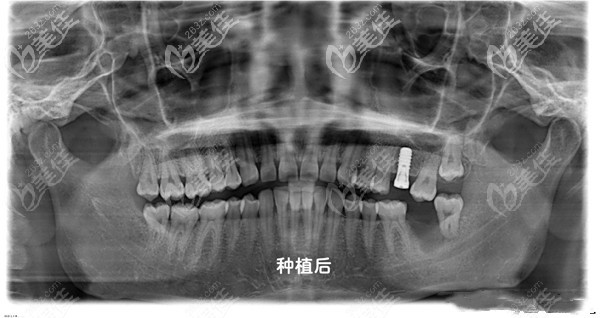

江医生表示:种植牙是通过医学方式将与人体骨质兼容性高的纯钛金属经过精密的设计,制造成类似牙根的圆柱体或其他形状。

以外科小手术的方式植入缺牙区的牙槽骨内,当人工牙根与牙槽骨密合后,再在人工牙根上制作牙冠。因不具破坏性且能获得与真牙相似的功能、结构及美观效果,被称为人类的第三副牙齿"。

而江晓亮医生也擅长单颗牙种植、多颗牙的微创种植,各类种植修复、固定修复、活动修复、半口及全口牙种植、前牙美学种植修复项目。